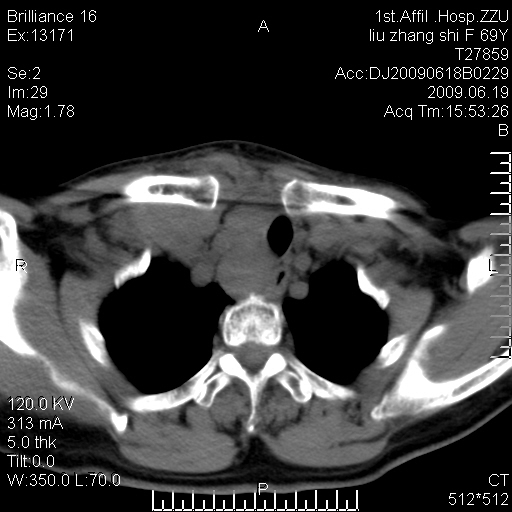

标题: CT26782:女,69岁,颈部占位,3天后公布病理结果。

【病理证实系列】女,69岁,颈部占位,有病理结果,3天后公布。(由于病例时间较久,临床资料不全,请网友见谅)本系列将有几百种常见、少见及罕见病例,均经病理证实。病例资料来自郑州大学第一附属医院。与网友共享,本人有空就发。

甲状腺癌并颈部淋巴结转移。感谢楼主的良苦用心,谢谢。

甲状腺癌并颈部淋巴结转移。

需与鼻咽癌鉴别!

支持甲状腺癌广泛侵及周围结构并颈部淋巴结转移。

鉴别:淋巴瘤、恶性神经源性病变、恶性纤维组织细胞瘤。

病理结果:颈部非霍奇金淋巴瘤。